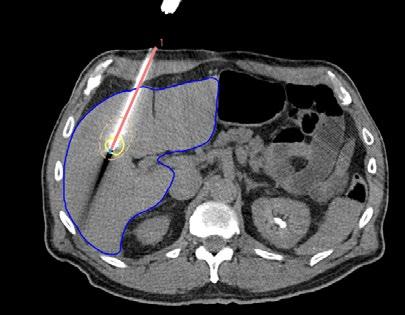

In liver ablation, a needle is inserted into the tumor, and the needle then burns away the tumor proceeding from its tip. RayStation 2024B includes an image guidance feature that ensures the needle is in the correct position so that the entire tumor is covered by the heat. The method was developed in a collaboration between RaySearch and MD Anderson Cancer Center, and showed considerably improved precision during liver ablation in a clinical trial.

A new module for image-guided liver ablation in RayStation was launched during the year. This means that RaySearch is now taking a step beyond the field of radiation therapy. Liver ablation is a treatment method in which a needle is inserted into the tumor, after which the tumor is destroyed by heat generated by microwaves or high-frequency radio waves.

One challenge of today’s method is that the tumor is not visible on the CT images taken after the needle is placed, and because the liver is deformed during needle insertion it is difficult to ensure that the needle is correctly positioned. This means there is risk that parts of the tumor could be left untreated.

The new module was developed in collaboration with the MD Anderson Cancer Center, which conducted a clinical trial with RayStation to test the method. The study was originally randomized, but after only a few patients had been treated, the researchers found that precision was significantly improved with image guidance, so they chose to remove the control group from the study prematurely. The results demonstrate that the method significantly improves precision in liver ablation.

The RayStation module supports image-guided liver ablation through three steps:

1. PLANNING – Before the needle is inserted, a contrast-enhanced CT image is taken to segment the tumor. The user can simulate the needle insertion to optimize the placement.

2. TARGETING – After the needle is inserted, but before the ablation is performed, a new CT image without contrast is taken. In this image, the needle is visible, but not the tumor. Through deformable image registration in RayStation, the position of the tumor from the previous contrast- enhanced image can be transferred to the current image, making it possible to verify that the needle is correctly positioned. If the tumor is not completely covered, the needle can be adjusted or an additional needle planned.

3. VERIFICATION – After treatment, a postoperative contrast-enhanced CT image is taken in which the ablation zone is visible as a darker area. On this image, the ablation zone is segmented and the tumor is transferred from the planning image to check that the entire tumor has been treated. Additional treatment can be carried out as needed.